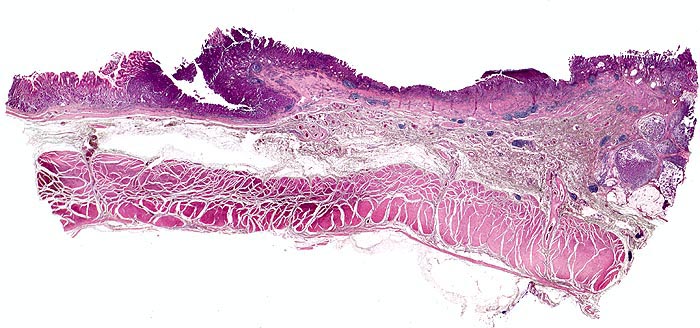

PathoPic – image database / PathoPic ID 5053 - Magenfrühkarzinom

Magenfrühkarzinom

Das Karzinom befindet sich am rechten Bildrand. Der expansiv wachsende Tumor infiltriert die Submukosa. Die Lamina muscularis propria wird nicht infiltriert. An der Basis zeigt das Karzinom eine ausgeprägte Schleimbildung.

Polypoider Tumor im Magenantrum.

Magenfrühkarzinome sind auf die Mukosa (Mukosatyp) bzw. Submukosa (Submukosatyp) beschränkt entsprechend einem Stadium pT1.